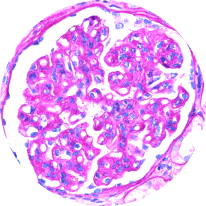

Light microscopy

Provides initial diagnostic evaluation, assessing patterns of glomerular injury. Does not distinguish between forms of glomerulonephritis2,21

Healthy glomeruli

MPGN pattern of injury

(C3G/IC-MPGN)